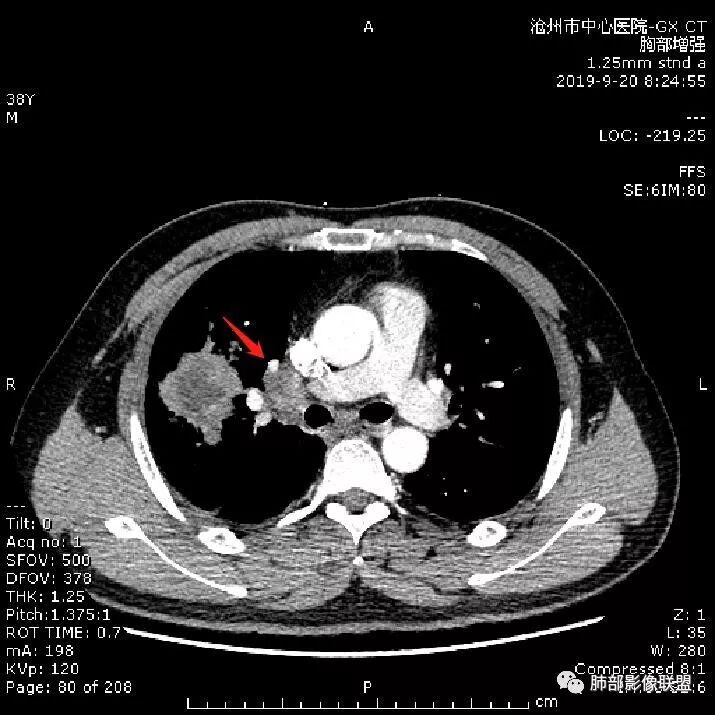

青年男性,肿瘤指标无异,右上中肺团片影,形态不规,跨叶生长,

病灶内见坏死,增强边缘强化,考虑炎性肉芽肿,TB,鉴别鳞。

年轻男性,咳嗽2月,痰中带血,胸痛,炎症指标稍高,肿标正常。影像,右肺上叶不规则团块影,浅分叶,伴边界不清磨玻璃影,从外周向内分布,局部胸膜增厚,病灶中央坏死,坏死边界尚清,空洞形成,空洞内壁光滑;考虑炎性肉芽肿性病变,结核可能,鉴别恶性肿瘤及真菌感染。病灶分布特点不考虑隐球。

右肺上叶不规则病灶,密度不均,有分叶,边缘不清,中央有坏死,坏死壁尚光滑,增强壁有强化,病灶有外朝内,整体收缩为主,慢性病程,考虑炎性病变,肺脓肿或者结核,淋巴结肿大,支气管截断,胸膜脂肪间隙变窄,加个鉴别恶性肿瘤。

38岁,男性,慢性咳嗽2月,右胸痛8天,无发热。白细胞高,肿瘤标志物不高。右上肺不规则块状影,周围有磨玻璃影,边界模糊,整体有膨胀感,分叶,与胸膜糊墙,可疑栽赃,增强肿块中央坏死,边界清,周边强化明显,强化区有低密度影,壁不规则,跨叶生长,支气管截断,伴支气管扩张,综合考虑腺癌

首先病灶示:跨尖、后、前三段,局部突入中叶;大家理解一下:是不是光滑的地方有叶裂,毛糙的地方没叶裂。

这个病变两侧受叶裂的局限,中央没有,如果是穿透叶裂的是否边缘也毛糙?事实上这叶裂边缘的叶裂是很光滑的,我倾向于这个是局部叶裂有缺陷;就是从缺陷处进来有病灶的本色:边缘毛糙;附近叶裂的阻挡,边缘光滑;既然怀疑是局部的缺陷就对良恶性没价值。

假如一个病灶直接跨越胸膜侵犯过来,应该边缘都很毛糙,不应该是最突出的地方毛糙,应该是逐步毛糙过去的,充其量越到外面毛糙越少;但事实上今天这个病变是一个很突兀的毛糙,突然间嘎然而止的毛糙;所以这个提示应该是从缺陷处跨过来的;还有今天的这个病例,病灶跨叶的部分对附近的胸膜是推移的,附近的胸膜还是很光滑,但是跨叶的病灶区很毛糙,提示跨叶部分存在胸膜缺陷可能;一般来说恶性肿瘤直接侵犯到对侧还是少的,如果这个地方你怀疑有缺陷,跨胸膜在诊断良恶性价值就不大了。